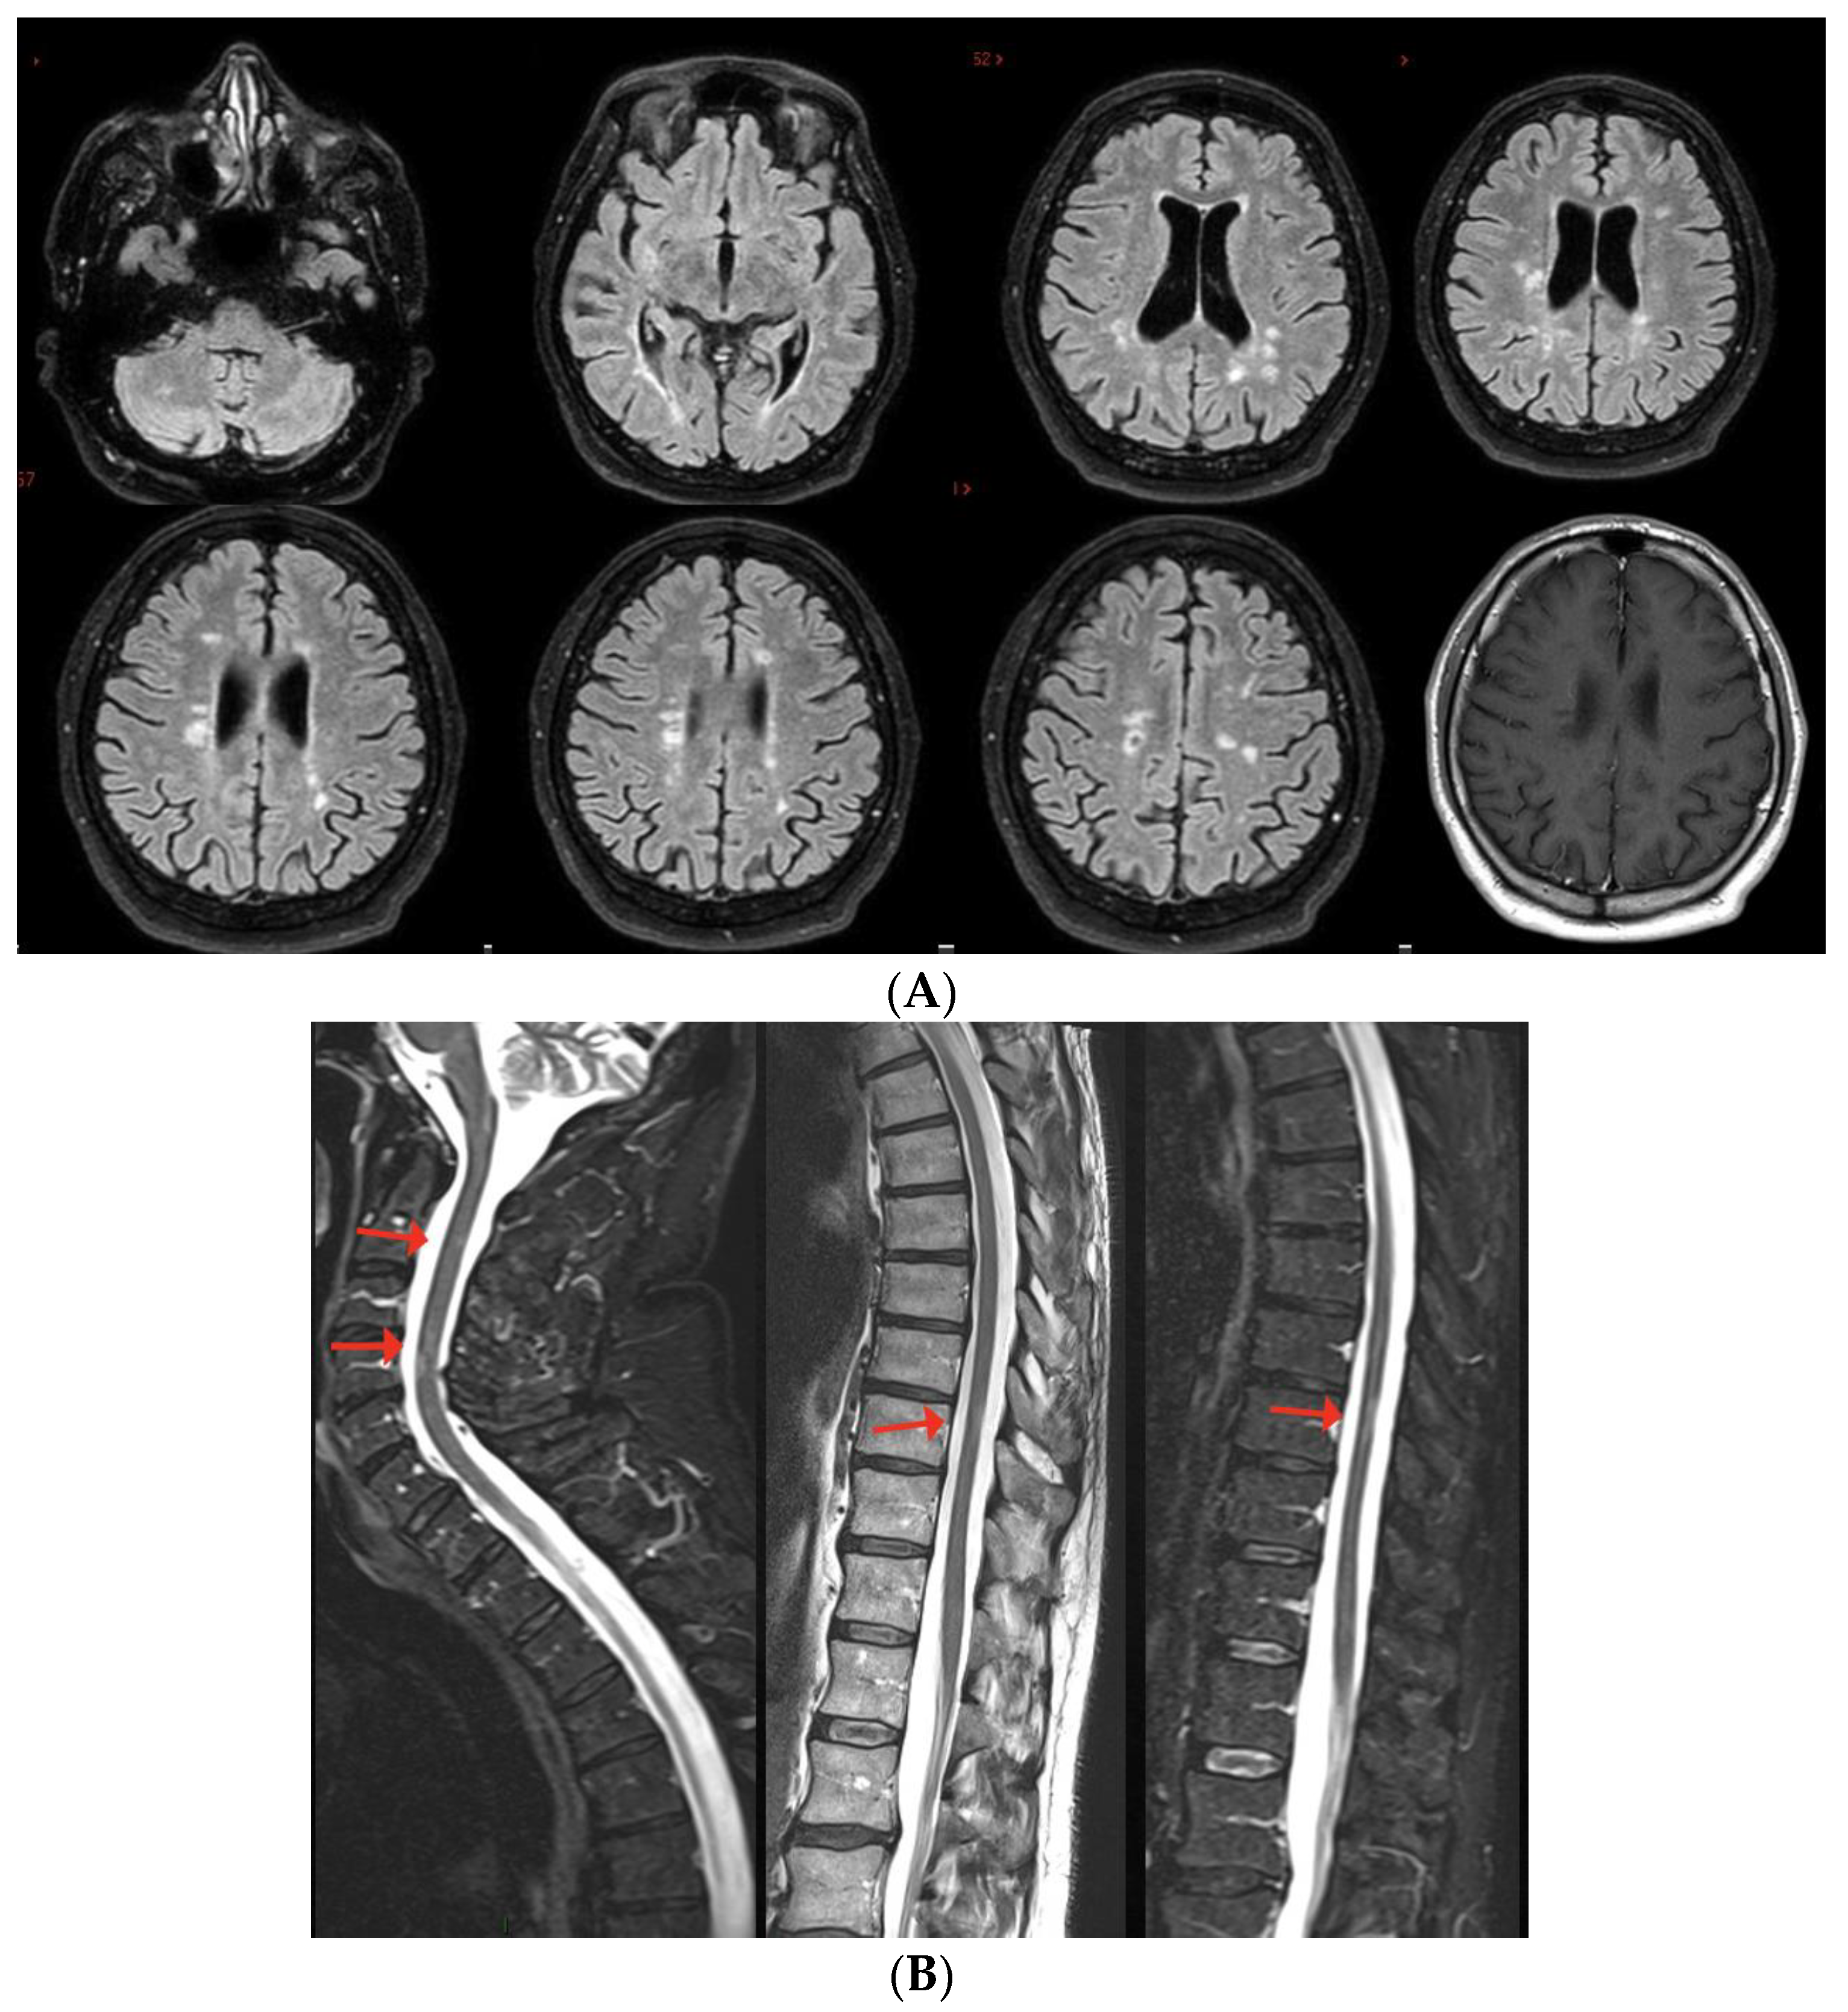

5. MS Relapses after Vaccine Exposure

| MS RELAPSE | ||||||||

| Rinaldi et al. [68] | BNT/1st | 2 weeks | Cerebellum/BS | ST | + | + | IFNb | NA |

| $ Al-Midfai et al. [71] | JJ/2nd | 2 weeks | Uncertain (unilateral motor deficit) | - | + | NA | - | NA |

| $ Maniscalco et al. [72] | BNT/1st | 2 days | Unilateral SM deficit | ST | + | NA | FTY | NA |

| Kataria et al. [73] | BNT/2nd | 3 weeks | ON + SC | ST | + | - | IFNß | NA |

| Seyed Ahadi et al. [74] | Sinopharm/1st | 2 days | Paraparesis and ataxia | BS | + | NA | - | NA |

| Kayat-Khoei et al. [64] 4 cases | mRNA vaccines 1st (1) and 2nd (3) | 1–3 weeks | ON (2) BS+SC (1) Possibly SC (1) | Brain (3) | + (new SC in 2 cases) | NA | NTZ (1) FTY (1) None (2) | NA |

| $ Nistri et al. [67] 14 cases | ChadOx/1st (2) mRNA/1st (7), 2nd (5) | 2 days–3 weeks | BS/cerebellum (4) SC (6) Possibly SC (6) | Brain (13) | + | + | + (9) - (5) | NA |

| D’apolito et al. [75] | BNT/2nd | 4 days | BS/cerebellum | + | - | + | FTY | NA |

| $ Fragoso et al. [49] 8 cases | BNT/1st | BS | Various | Some | NA | NA | Various DMT (7) | NA |